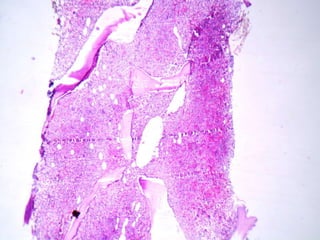

A 55-year-old female presented with pancytopenia and spleenomegaly. Bone marrow aspiration was dry but imprint smears and biopsy showed relevant findings. A 30-year-old male presented with upper GI obstruction and was found to have an ulcerative duodenal lesion. He underwent Whipple's operation and imaging found enlarged pancreaticoduodenal and paraaortic nodes with mild hepatosplenomegaly. Micrographs of lymph nodes were submitted. A 65-year-old male presented with abdominal discomfort and CT scan showed multiple enlarged retroperitoneal and mesenteric nodes without hepatosplenomegaly; a biopsy of a retroperitoneal lymph node was submitted.